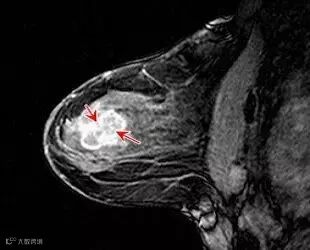

【乳腺病】

【乳腺肿块】

【乳腺增生】

【乳腺纤维瘤】